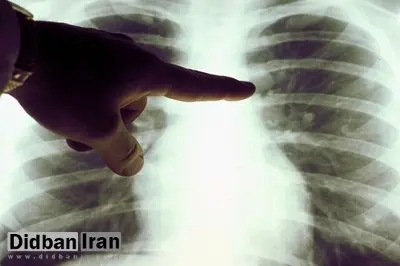

علائم انواع سرطان ریه

۲ نوع اصلی سرطان ریه وجود دارد: سرطان ریه سلول کوچک (SCLC) و سرطان ریه سلول غیر کوچک (NSCLC).

به گزارش سایت دیده بان ایران ؛سرطان ریه سلول غیر کوچک شایع تر است و حدود ۸۵ درصد از کل موارد سرطان ریه را تشکیل میدهد.